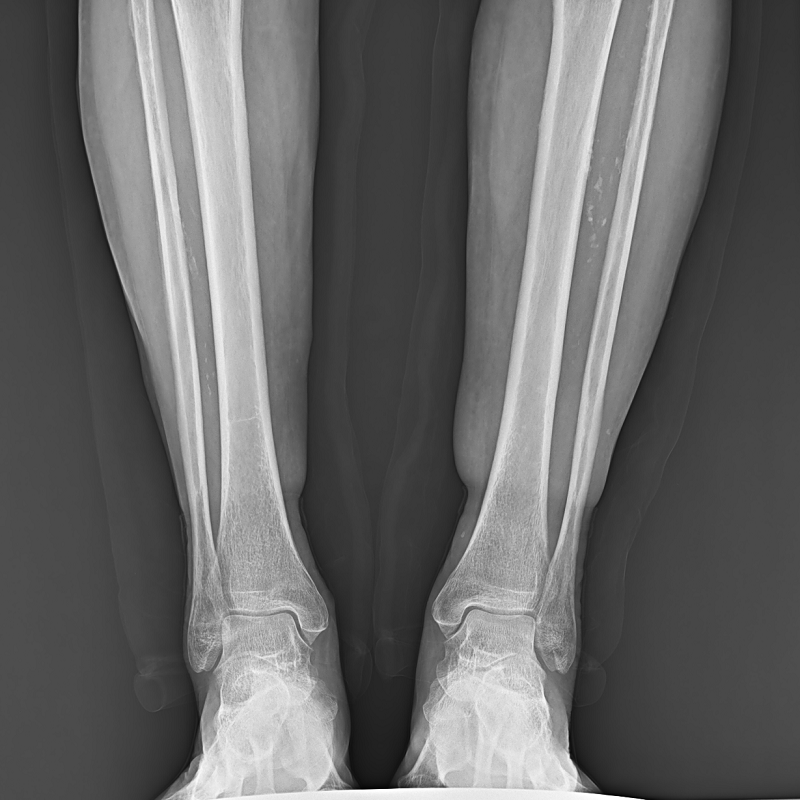

●呈現(xiàn)全下肢或全脊柱圖像

●在脊柱及下肢畸形矯正手術(shù)治療中,為術(shù)前方案制定和術(shù)后復(fù)查提供精準(zhǔn)測量

●有效解決傳統(tǒng)X光片不能一次成像問題,為患者提供更加優(yōu)質(zhì)的醫(yī)療服務(wù)

點(diǎn)片裝置可實(shí)現(xiàn)大范圍縱向移動,高效完成各部位、全身拼接等檢查需求